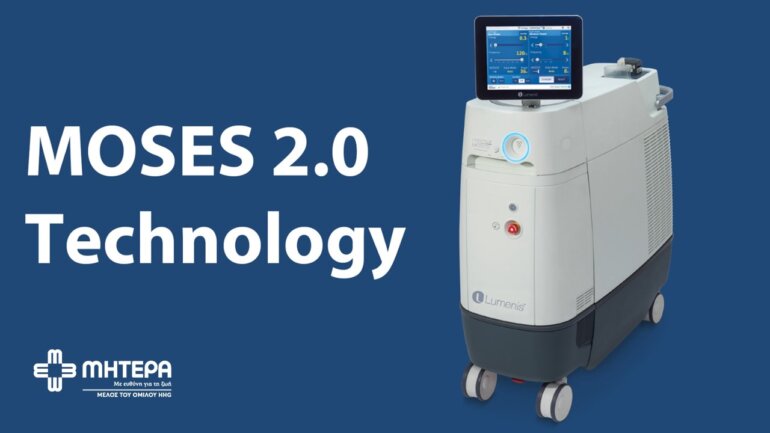

Kαλοήθης υπερπλασία του προστάτη: Σύγχρονη και οριστική λύση

Γρήγορο, αξιόπιστο και αποτελεσματικό, το MultiPulse HoPLUS παρέχει απαράμιλλη ακρίβεια και ασφάλεια σε όλες τις φάσεις της χειρουργικής επέμβασης.